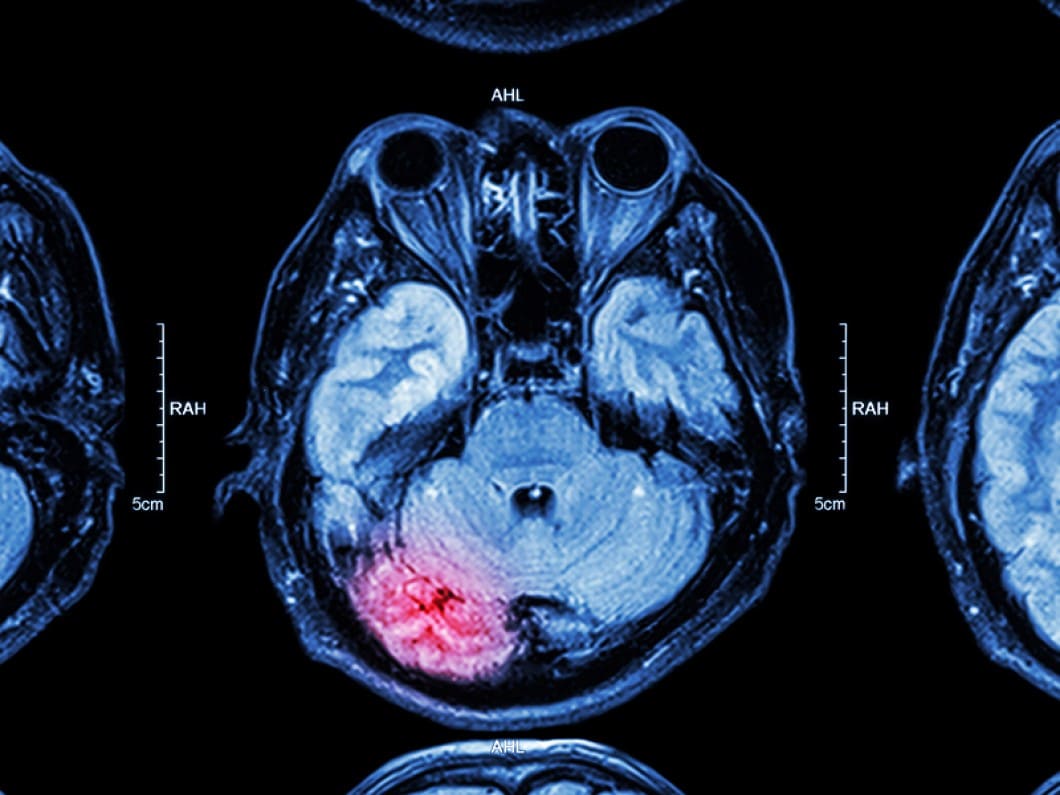

Few medical incidents are scarier or more life-threatening than a traumatic brain injury (TBI). Data shows that 1.37 million emergency room visits, 275,000 hospitalizations, and 52,000 deaths occur each year as a result of TBI.

There are dozens of potential causes of TBI. According to the Neurological and Brain Injury Section of Davis, Saperstein & Salomon, five of the most common include motor vehicle accidents, slips and falls, sports and recreation accidents, workplace accidents, and defective products.